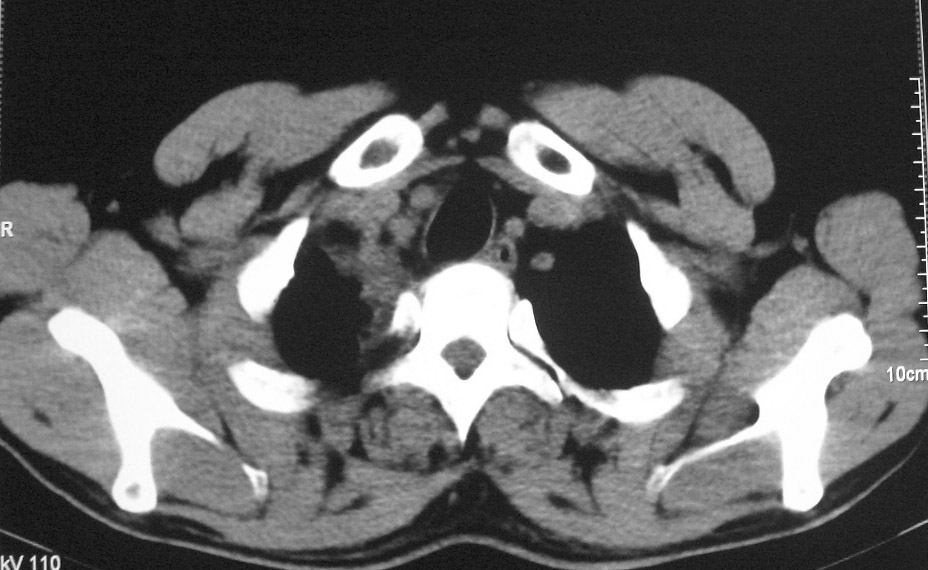

右肺上叶中央型肺癌并上叶肺不张、纵隔淋巴结肿大

右上叶支气管后壁明显增厚,支持右肺上叶中央型肺癌伴右上叶肺不张、纵隔淋巴结肿大。

考虑右上肺癌并肺不张,纵隔淋巴结转移

右上叶支气管开口变窄,纵隔见肿大的淋巴结。支持右上叶中心型肺癌并右上叶不张纵隔淋巴结肿大。

右肺上叶中央型肺癌并上叶肺不张、纵隔淋巴结肿大.右侧少量胸腔积液。